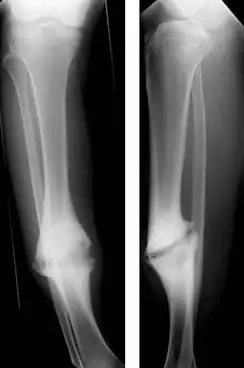

Hypertrophic nonunion of the tibia | |

In a hypertrophic nonunion, the fracture site contains adequate blood supply but the fracture ends fail to heal together.[6] X-rays show abundant callus formation. This type of nonunion is thought to occur when the body has adequate biology, such as stem cells and blood supply, but inadequate stability, meaning the bone ends are moving too much. Typically, the treatment consists of increasing stability of the fracture site with surgical implants.[7]